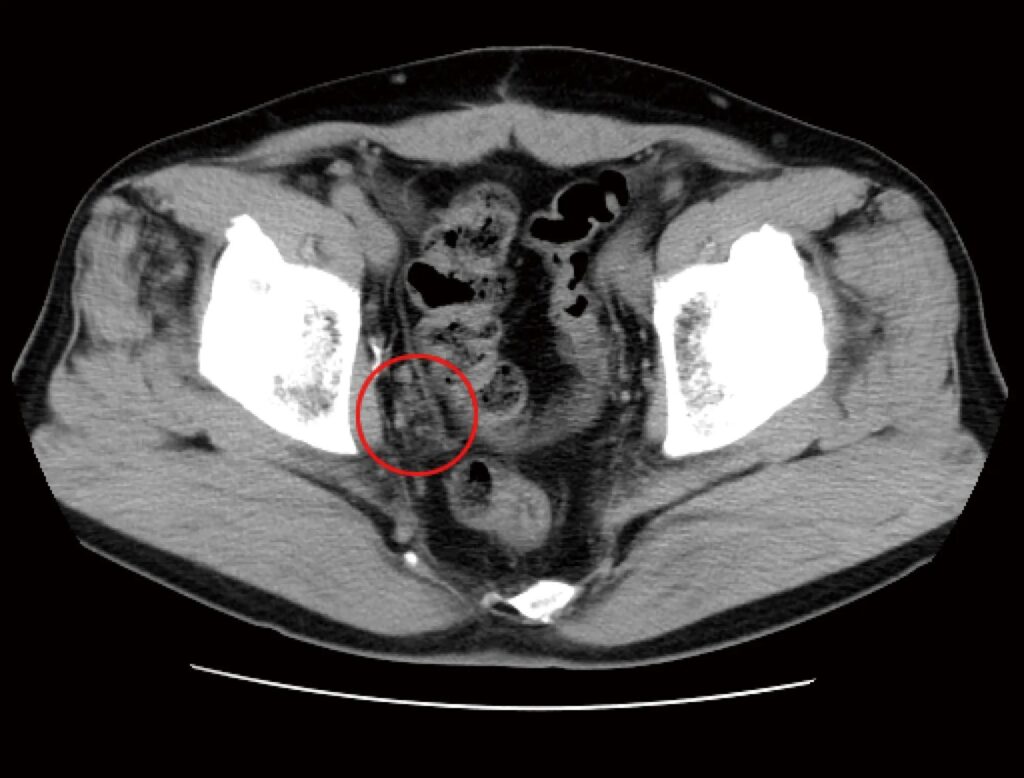

免疫治療前に拝見したCT検査によると、骨盤の底部/右側(写真では左・赤マル部分)を中心に、複数のリンパ節転移によって形成されたがん病巣が認められました。

前立腺がんリンパ節に転移したCT画像